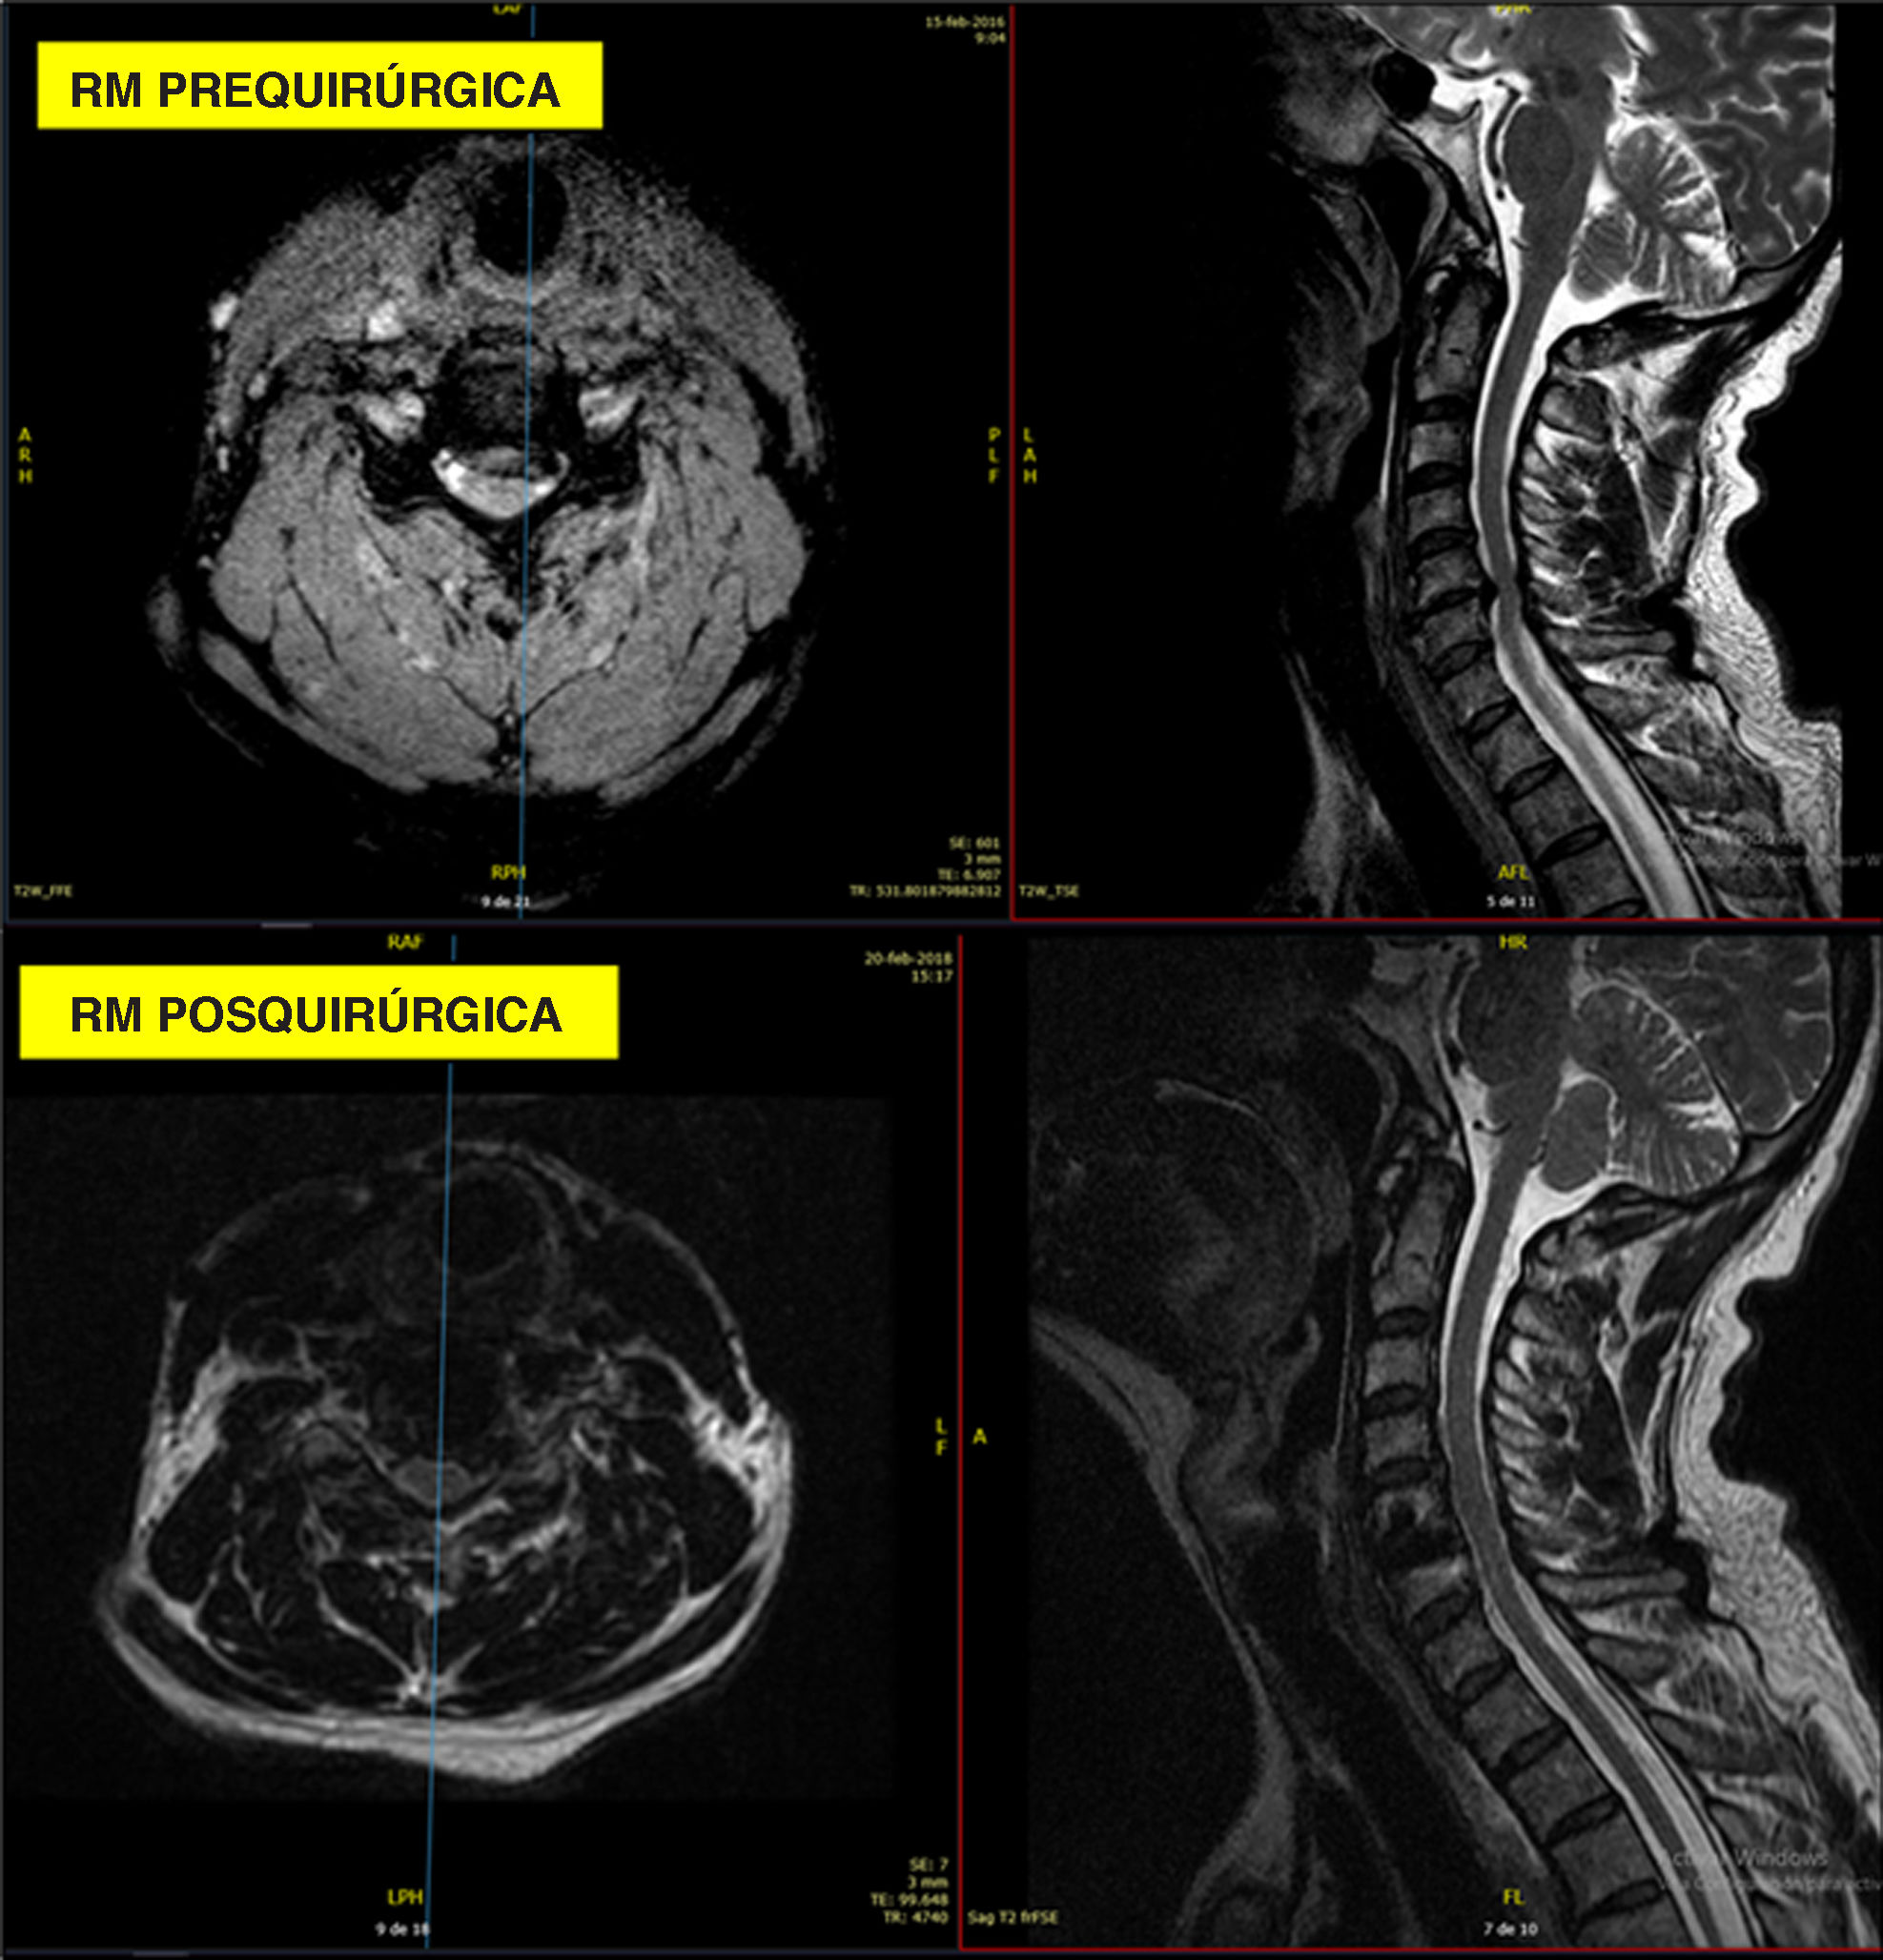

Criterios de valoración radiológicosLas radiografías dinámicas de flexión/extensión (fig. 3) no demostraron movimiento segmentario en ningún caso en los niveles operados en el seguimiento a largo plazo. Las imágenes de resonancia magnética (RM) pre- y postoperatorias representativas (fig. 4) confirmaron una descompresión adecuada con un artefacto de susceptibilidad mínimo.

Caso 3: RM cervical pre- y postoperatoria. (A) Imágenes preoperatorias axiales y sagitales ponderadas en T2 que demuestran la estenosis en el nivel operado. (B) Imágenes postoperatorias axiales y sagitales ponderadas en T2 que muestran una descompresión adecuada con un artefacto de susceptibilidad mínimo de la jaula de PEEK-titanio anclada.